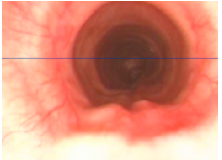

Tracheal hypoplasia